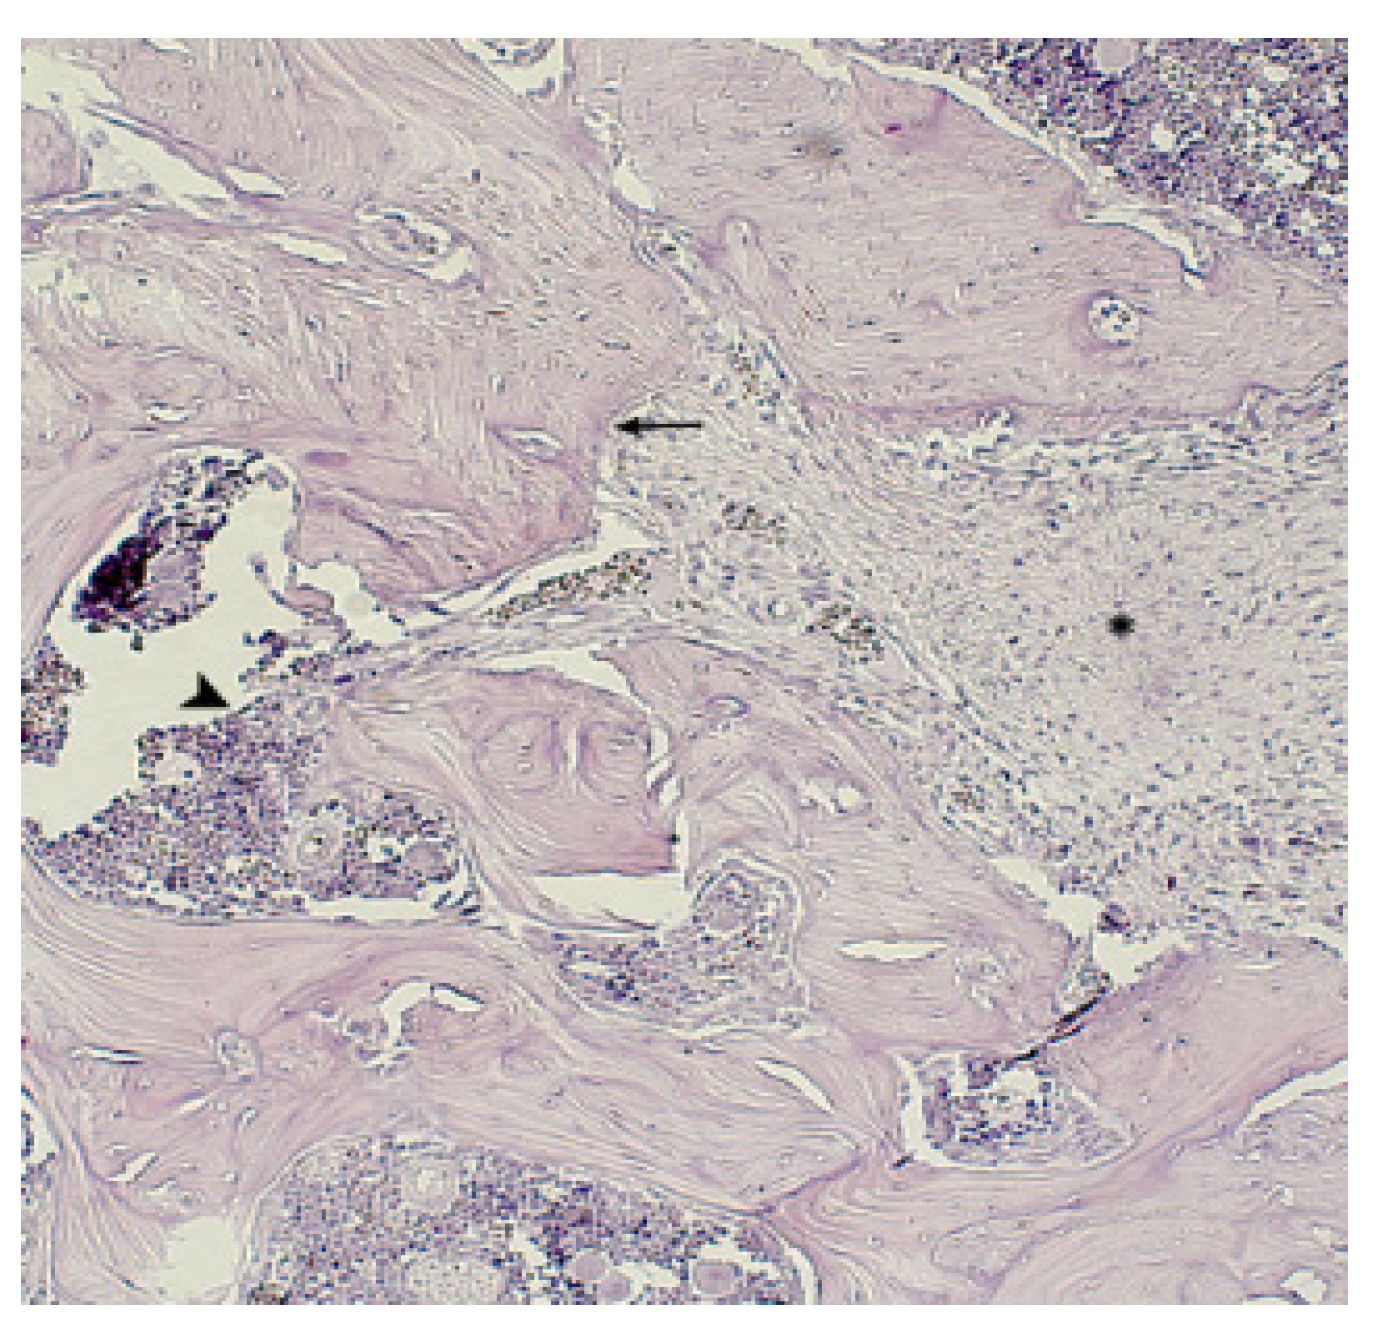

) are detected, in the bone tissue “isolated” osteocytes (^). Hematoxylin-eosin staining. Magnification x480.